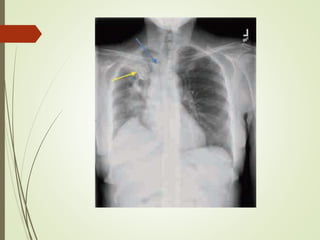

 Chest xray

Diagnostic approach  Chestxray  Sputum examination  Blood culture sensitivity: high risk patient as neutropenic, asplenia,complement deficiency,CLD or severe CAP  Antigen test: for pneumococcal and certain legionella antigen in urine  PCR: detect neucleic acid of legionella spp., M.pneumonia